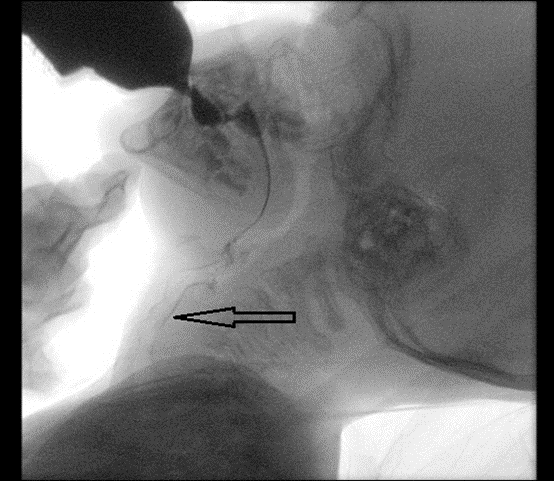

Dítě s podezřením na dysfagii vyšetřujeme v rámci Kliniky dětské otorinolaryngologie FN Brno v poradně pro poruchy polykání. V základním dysfagiologickém týmu je otorinolaryngolog a klinický logoped. Poskytujeme kompletní screening a klinické vyšetření dysfagie, včetně vizualizace polykacího procesu endoskopicky (FEES) a/nebo radiologickou metodou (VFSS) a nastavíme dítěti terapii. Platforma superspecializované péče na půdě fakultní nemocnice je ideálním místem k poskytovávání komplexní péče o děti s dysfagií. Zásadní je spolupráce s dalšími obory, zejména pediatrií, gastroenterologií, neurologií, fyzioterapií, chirurgií a radiologií.